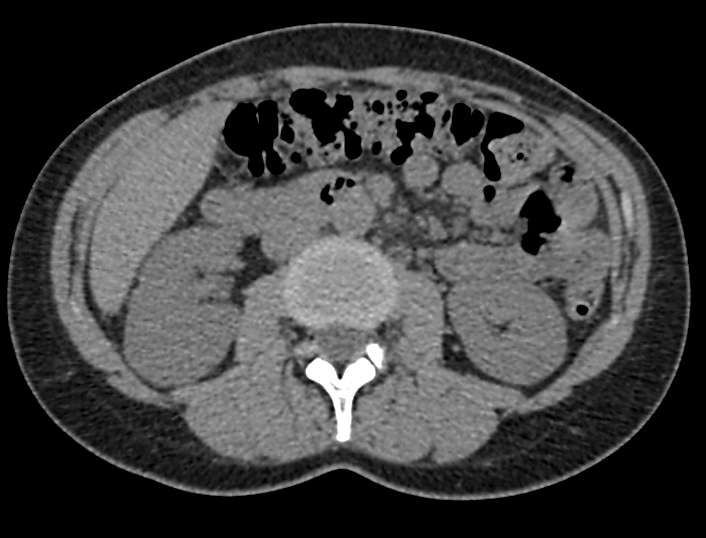

Мультиспиральная компьютерная томография почек и мочевыводящих путей является высокоинформативным методом исследования, основанном на использовании воздействия рентгеновских лучей на органы и ткани человека. Методика предусматривает послойное сканирование области почек, мочевыводящих путей и получение снимков исследуемой области в мельчайших подробностях.

Для улучшения визуализации патологических очагов в некоторых случаях дополнительно применяется контрастное усиление. Для этого пациенту внутривенно вводится йодсодержащее контрастное вещество, которое накапливается в патологически измененных участках и вызывает их яркое контрастирование на фоне здоровых тканей.

МСКТ почек и мочевыводящих путей с контрастированием позволяет выявить опухолевые образования на ранних стадиях, отличить доброкачественную опухоль от злокачественной, определить размеры опухоли, точную локализацию и степень распространения в окружающие ткани. Компьютерная томография почек с внутривенным болюсным контрастированием необходима для определения тактики лечения и объема оперативного вмешательства.